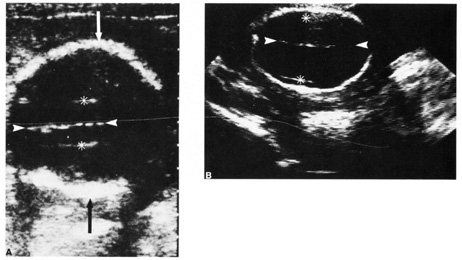

Diagnostic ultrasound is widely used in the assessment of pregnancy and the fetus. Although clinical benefits of routine ultrasonography during pregnancy have not been established, approximately 70% of pregnancies in the United States undergo ultrasound evaluation.30 Because most instruments used in diagnostic ultrasonography produce energies no greater than 10 to 20 mW cm2 (safety defined as less than 100 mW cm2), ultrasound is considered generally safe. No harmful biologic effects on instrument operators, pregnant women, fetuses, or other patients have been found. Infants exposed in utero have shown no significant differences in birth weight or length, childhood growth, cognitive function, acoustic or visual ability, or rates of neurologic deficits (see Fig. 6).

Fig. 6. A: First-trimester twin intrauterine gestations. Ultrasound examination of the pregnant uterus (arrowheads) shows the “owl eyes” characteristic of early twin pregnancies. B: Maternal urinary bladder. (Courtesy of Alfred B. Kurtz, MD)

Fetal number (Fig. 6)

First trimester ultrasound may be performed transabdominally or transvaginally. Table 7 lists the components of a first trimester ultrasound. A crown–rump length, done between 7 and 13 weeks, can define a gestational age to within 5 days (Fig. 7).

Fig. 7. First trimester ultrasound showing crown–rump length.